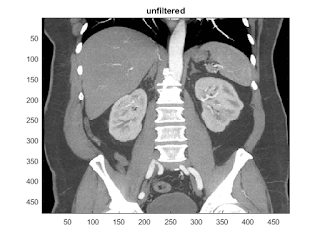

filtering demo on the CT data

clf;

imagesc(I);colormap(gray);

title('unfiltered');